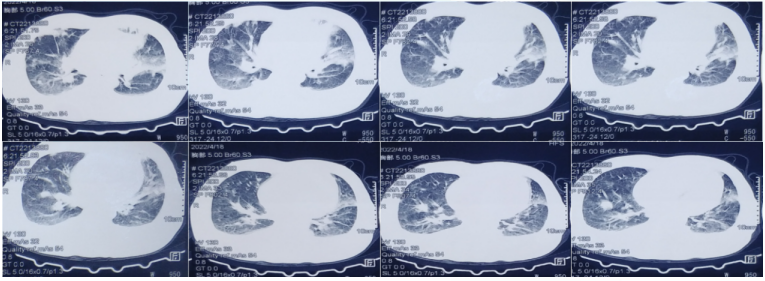

• 胸部CT:双肺渗出性病变,双侧胸腔积液(图1)

1  患者胸部CT(2022-04-18)